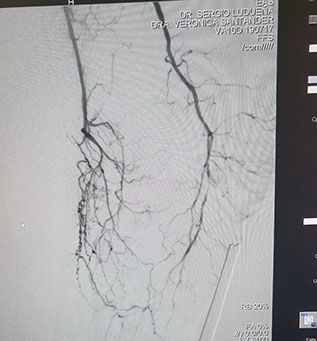

Se realizó un abordaje híbrido con el Dr. Alejandro Flores, y se re canalizó ambas arterias tíbiales. Procedimiento inédito en nuestra provincia.

Las imágenes siguientes son previas al procedimiento y posterior se ve ambas arterias tíbiales permeables, y circulación en el pie